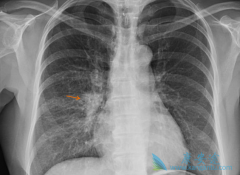

肺癌是当前世界上严重危害人类健康的恶性肿瘤,现已成为世界上因肿瘤致死的首要病因。在许多国家肺癌的发病率都呈上升趋势,尤其是在我国的城市当中其发病率和死亡率已上升为第一位。5年生存率低于15%,肺癌复发是导致死亡率高的主要原因。那 肺癌复发症 ...

• 肺癌的早期症状不容忽视越早治疗效果越好

肺癌的早期症状不容忽视越早治疗效果越好

肺癌的死亡率非常高,因此人们都非常担心会患上肺癌这种疾病,肺癌的发生会给患者带来的是无尽的痛苦,但是如果我们能够及时的发现肺癌疾病的症状的话,我们就可以及时的进行治疗,减少伤害,下面我们就一起了解一下 肺癌早期的症状 有哪些吧!   非常 ...